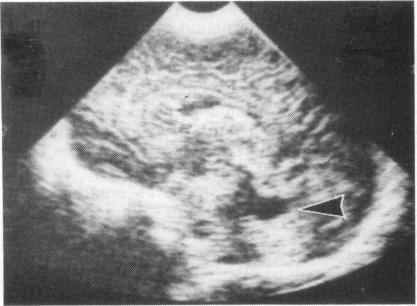

Five children with features of Joubert's syndrome and Leber's amaurosis are described. The presenting symptoms were panting tachypnoea in the newborn, prolonged apnoeic attacks in the neonatal period (in both of identical twins), global developmental delay, and failure to develop vision. Three children had multiple hemifacial spasms, such as have been seen in Joubert's syndrome, and the same three had cystic dysplasia of the kidneys. Necropsy confirmed the retinal and renal pathology, together with agenesis of the vermis and brainstem dysgenesis in the identical twins. It is concluded that a gene for Leber's amaurosis may commonly manifest itself as the specific hind brain malformation underlying Joubert's syndrome. In infants with respiratory irregularities (especially rapid panting), hemifacial spasms, or developmental delay, absence of the cerebellar vermis should be specifically sought by ultrasound and computed tomography, and the electroretinogram measured, whether or not impaired vision is clinically evident.

本文描述了5例具有儒贝尔综合征(Joubert's syndrome)和莱伯先天性黑矇(Leber's amaurosis)特征的儿童。其首发症状为新生儿期气喘性呼吸急促、新生儿期(同卵双胞胎均出现)长时间呼吸暂停发作、全面发育迟缓以及视力发育障碍。3名儿童出现了儒贝尔综合征中可见的多次半面痉挛,且这3名儿童均患有肾囊性发育异常。尸检证实了视网膜和肾脏病变,以及同卵双胞胎中的小脑蚓部发育不全和脑干发育异常。结论是,莱伯先天性黑矇的一个基因可能通常表现为儒贝尔综合征潜在的特定后脑畸形。对于有呼吸不规则(尤其是急促气喘)、半面痉挛或发育迟缓的婴儿,无论临床上视力是否明显受损,都应通过超声和计算机断层扫描专门检查小脑蚓部是否缺失,并测量视网膜电图。